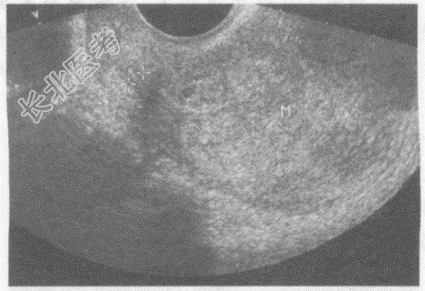

- 单项选择题临床资料:女性患者, 62岁,自述绝经10年, 阴道不规则出血半年。

超声综合描述:经阴道扫查子宫后位, 增大,子宫内膜不均匀性增厚, 与子宫肌层分界不清,侵及肌层深度>50%, 接近浆膜层,CDFI: 内可见丰富动、静脉血流信号,呈低阻型动脉频谱。见下图及彩图。

超声提示: A、子宫内膜腺瘤样增生

B、子宫内膜息肉

C、子宫内膜癌(侵及肌层>50%)

D、子宫肌瘤

E、子宫腺肌症